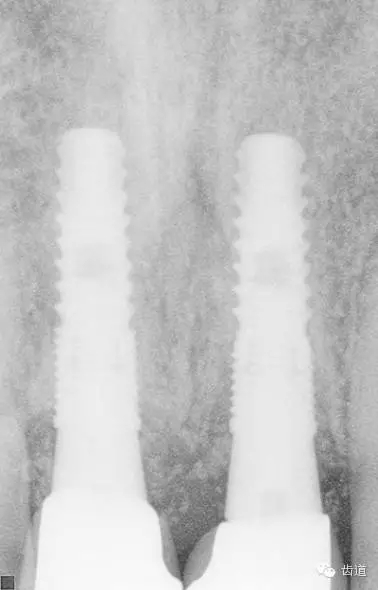

術(shù)后CT

戴牙后CT